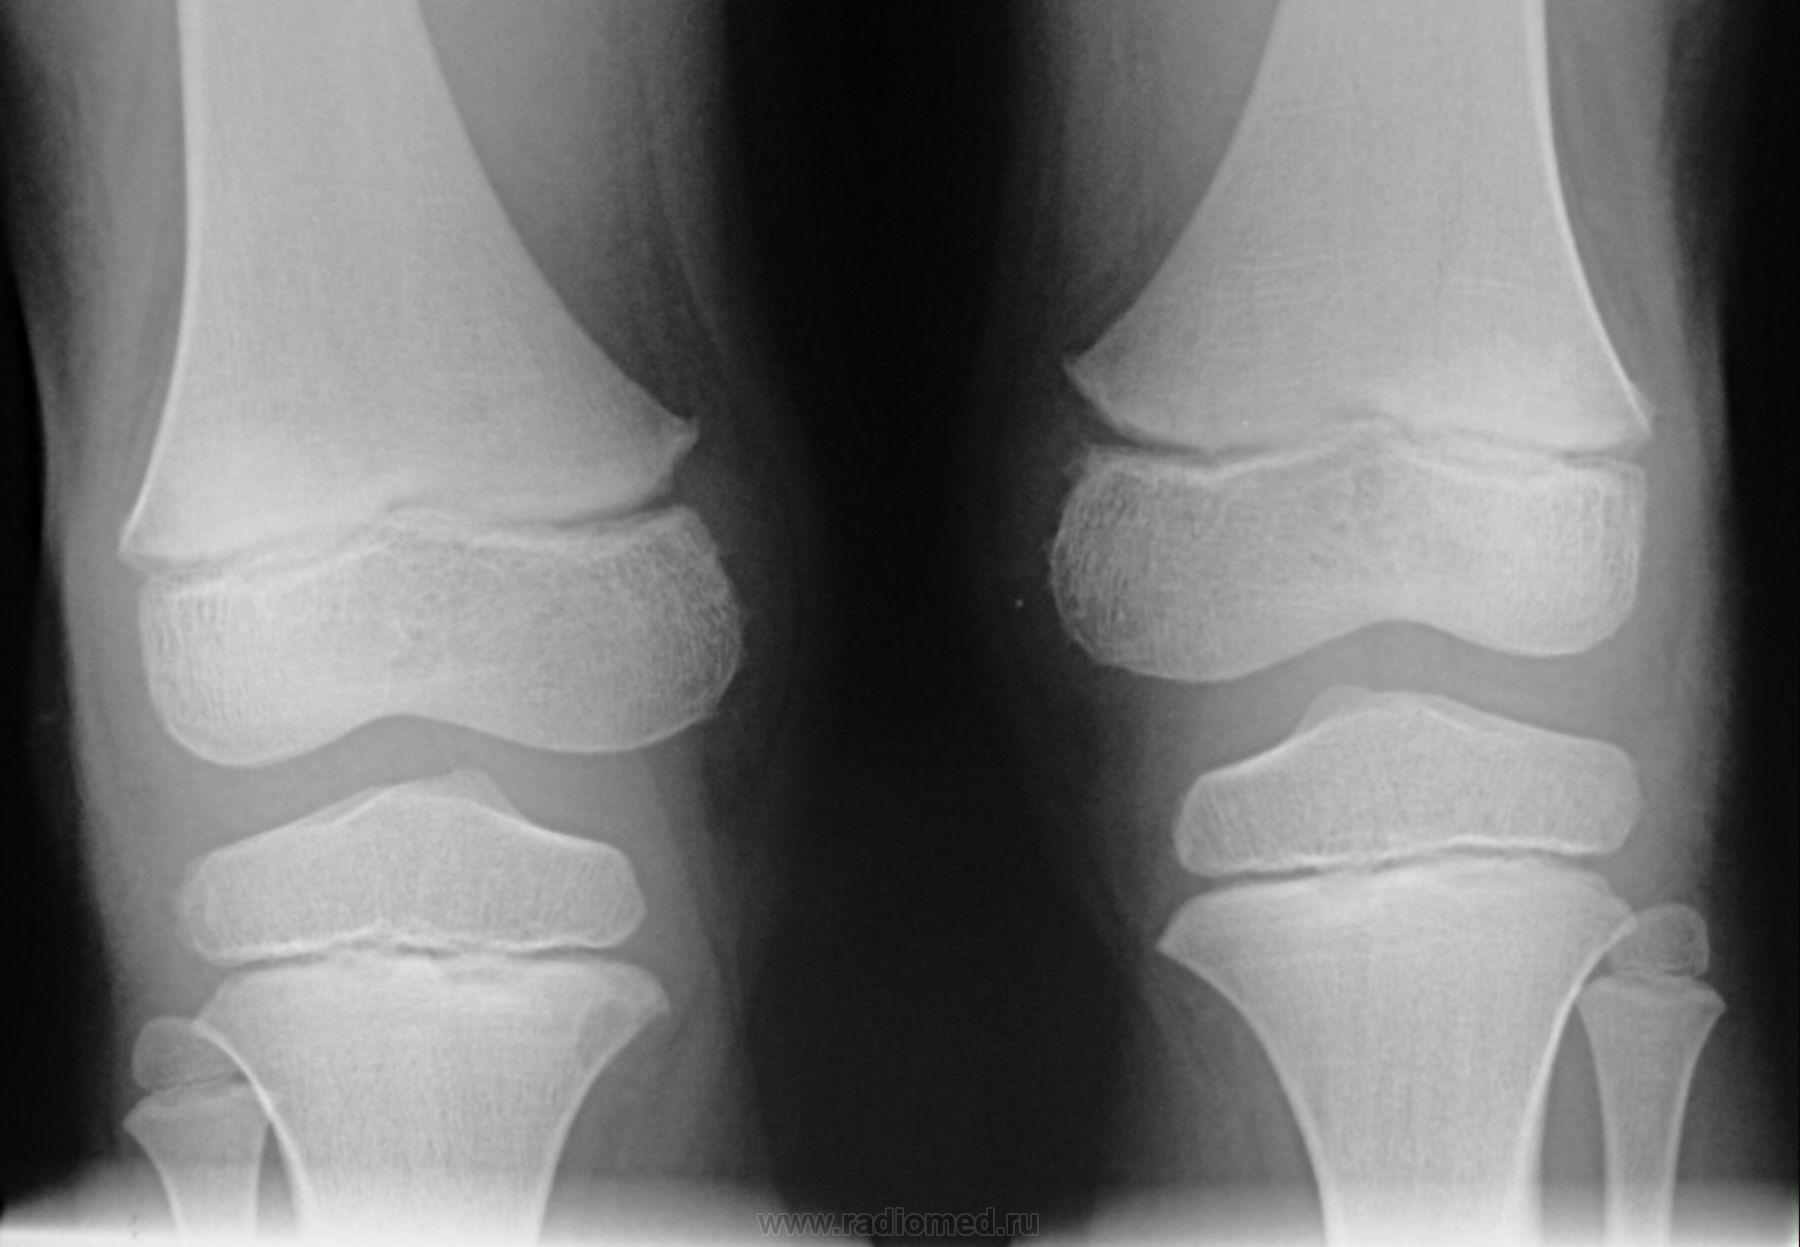

Пол пациента: Мужской пол Тип патологии: Доброкачественное новообразование, киста Область исследования: Скелетно-мышечная система Методы исследования: Rg Мальчик 2003 года рождения беспокоят осалгии направлен ортопедром, не нравиться киста, что порекомендуете? https://radiomed.ru/sites/default/files/styles/case_slider_image/public/user/1787/dsc01263.jpg?itok=28ZCqaKG ID:11719 Втр, 01/02/2011 - 12:15 #1 Vikkur Не на сайте Был на сайте: 4 года 9 месяцев назад Зарегистрирован: 24.09.2009 - 14:34 Публикации: 1749 ctПриложения: Виктор.